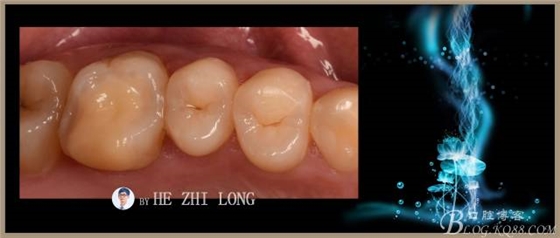

術(shù)后即刻調(diào)合拋光照片:(由于鑄瓷嵌體很難達(dá)到烤瓷嵌體的色澤,因此從牙本質(zhì)到牙釉質(zhì)的色澤沒有很好的過度,稍有點(diǎn)遺憾。)

術(shù)前術(shù)后對(duì)比照片:

術(shù)后半個(gè)月照片: